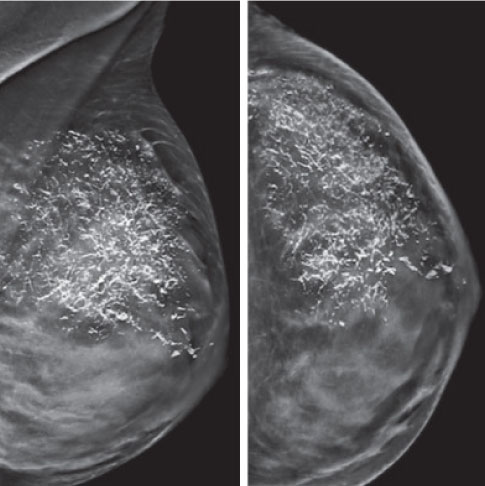

A mammogram screening is a safe, low-dose X-ray picture of the breast where two X-ray pictures of each breast are taken.

In our mammography section, mammography is performed by a specially trained female radiology technologist. The breast is compressed between two plates attached to a specially designed X-ray machine. This may cause some discomfort but it is a relatively painless procedure. Compression lasts only for a few seconds and the entire procedure of mammography takes about 20 minutes. The technologist will guide you throughout the procedure and will answer all your queries.

• A low dose of radiation, high resolution with superior image quality, AEC (automatic exposure control) and optimized compression with automatic decompression are the unique features of our machine.